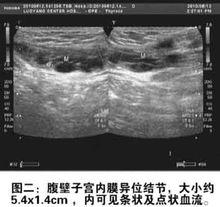

腹壁子宮內膜異位症屬於特殊部位的子宮內膜異位症,隨著剖宮產率的上升,腹壁子宮內膜異位症的發病率逐年上升,足月剖宮產腹壁子宮內膜異位症發生率為0.03%~0.40%,發病原因一般認為是在剖宮產手術時,肉眼難以發現的子宮內膜碎片,散落在腹壁切口,並種植於其中造成的。臨床症狀是腹壁切口處有硬結或腫塊,絕大多數腫塊與月經密切相關,經前及月經時腫塊增大疼痛加重,經後疼痛緩解而且腫塊縮小。超聲檢查可幫助診斷。

除了醫生通過雙手進行觸診檢查,超聲檢查套用比較簡單,沒有創傷,可以測量病灶的大小,侵犯和浸潤的深度,以及病灶和周圍組織結構的關係。CT、MRI 也可用於術前評估,通常在病灶巨大,或者侵犯較深,或者可疑有惡性變的情況下才會使用。